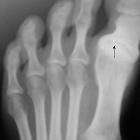

Osteochondritis

dissecans and Osgood Schlatter disease in a family with Stickler syndrome. Patient 1: Anteroposterior at age of 17 years foot radiograph showed progressive hallux varus with marked osteoarthritis of the base of the first toe.